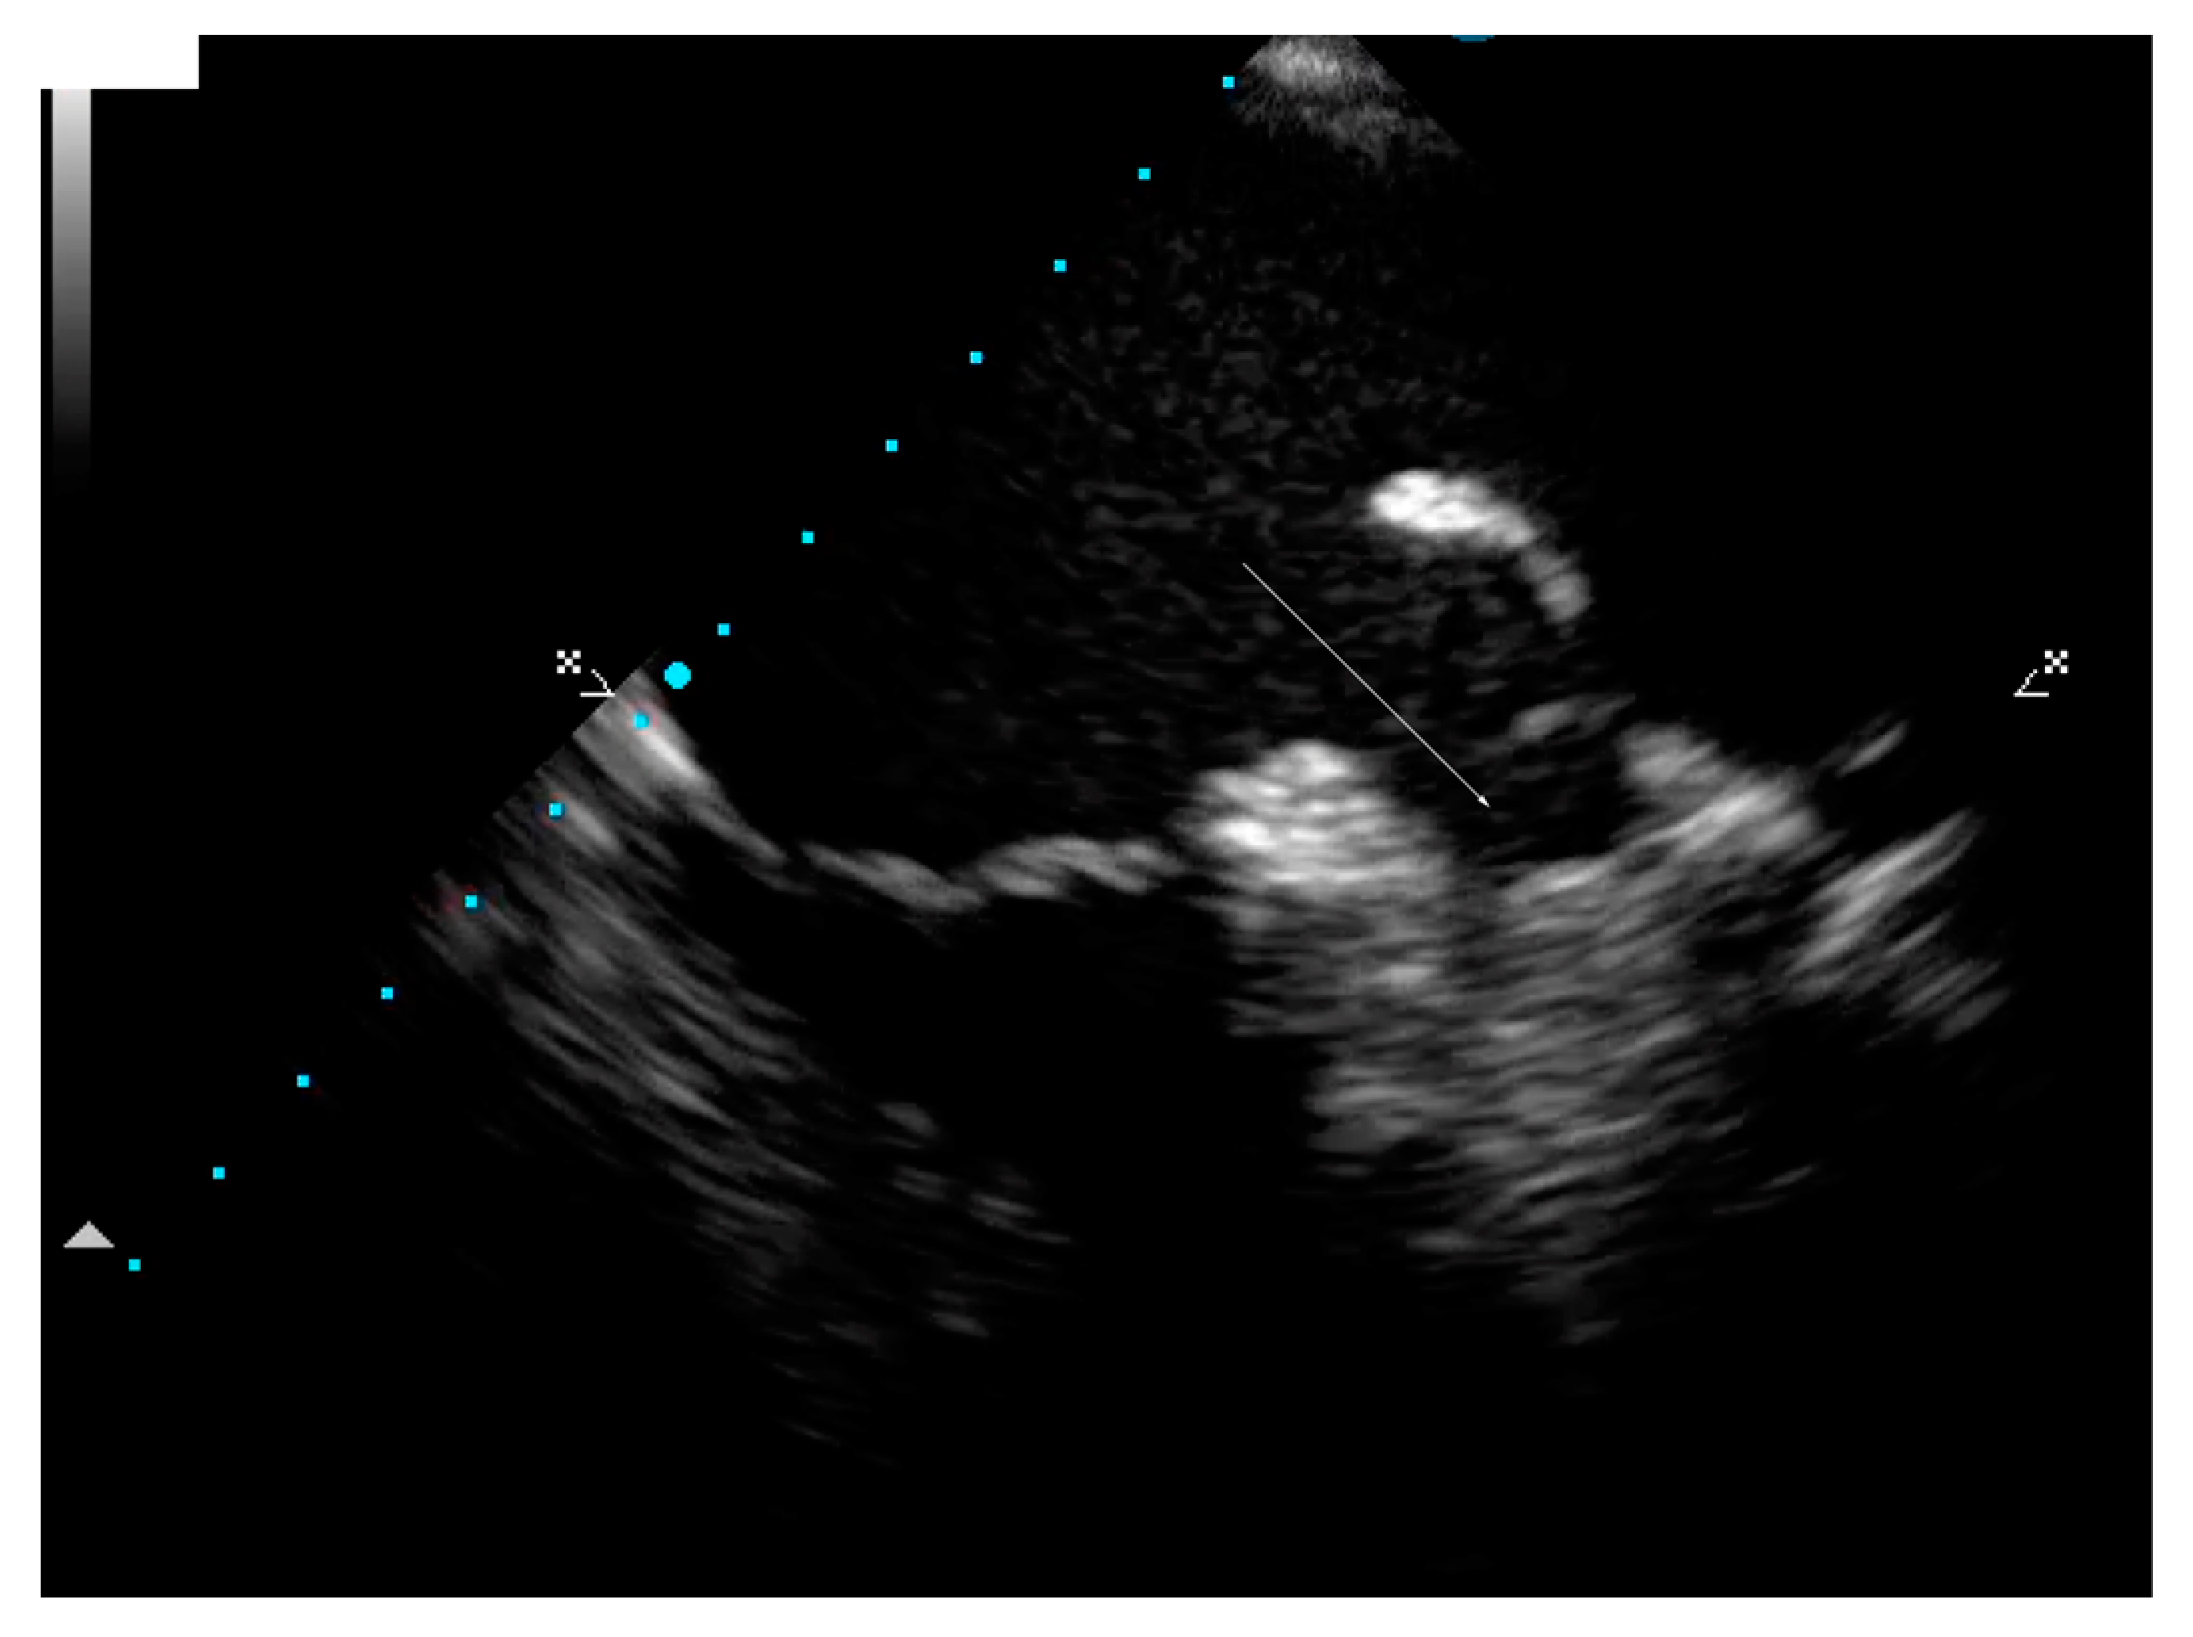

| March 2021, age 45 | First episode of decompensated heart failure, NYHA III-IV class; A new episode of persistent AF, duration longer than two months | Management of failure according to guidelines; TEE not performed due to INR not being in target; Asymmetric left ventricular hypertrophy and reduced ejection fraction noted; Further diagnostic work-up recommended—cardiac magnetic resonance (CMR) and genetic testing; Test for Anderson–Fabry disease—negative; CMR study positive for cardiomyopathy with diffuse fibrosis, possibly hypertrophic or infiltrative.  | At admission: Amiodarone 400 mg; Torasemide 20 mg; Irbesartan 75 mg; Acenocoumarol; At discharge: Torasemide 50 mg; Spironolactone 50 mg; Acenocoumarol; Bisoprolol 5 mg; Sacubitril/valsartan 2 × 24/26 mg; Allopurinol 150 mg; Dapagliflozin 10 mg  |

| IVSd | PWLVd | IVSd/PWLVd | LV EDD | LV ESD | LV EDV | LV ESV | LVEF |

| 16–17 mm; | 8 mm; | 2 | 48 mm | 40 mm | 163 mL | 98 mL | 35–40% |

| LV GLS | PSD | MV E-wave | e’sept. | e’lat. | E/e’ ratio | TAPSE | IVC |

| 12.2% | 57.2 ms | 1.01 m/s | 0.06 m/s | 0.08 m/s | 14.42 | 16 mm | 20 mm, no collapse |

| RV basal diameter | RV EDA | RV ESA | RV FAC | RVFW | PA AT | TR Vmax | Kinetics |

| 41 mm | 21.4 cm2 | 14 cm2 | 35% | 4 mm | 148 ms | 2.2 m/s | Diffuse hypokinesia |